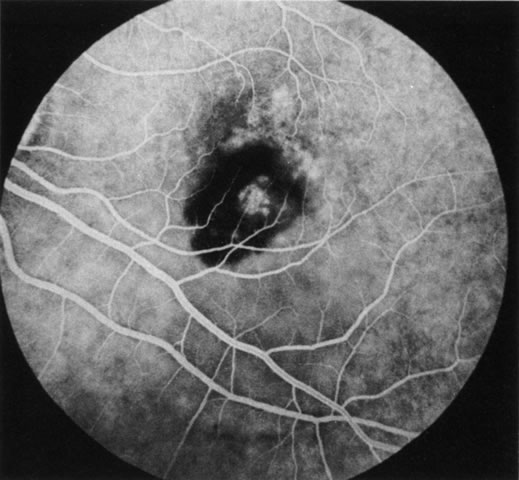

Age-related macular degeneration (AMD) may be divided into two types. Nonexudative (“dry”) AMD has several morphologic forms, including “hard” discrete drusen, shallow retinal pigment epithelial detachments associated with thickened Bruch's membrane (“soft” drusen), and geographic atrophy (GA) of the retinal pigment epithelium (RPE).3 On FA the area of GA appears hyperfluorescent for window defect from the early frames of the angiogram, with late staining of the underlying sclera (Fig. 1). However, these pathologic changes can usually be assessed by clinical examination, and FA is generally not necessary to diagnose nonexudative AMD. An exception is cuticular drusen, which may appear clinically as a subtle disturbance of the RPE; FA reveals multitudes of small, discrete drusen described as “stars in the sky” (Fig. 2). The second type of AMD, which is associated with soft drusen, is known as exudative (“wet”) AMD. It is due to a choroidal neovascular membrane that has incompetent vessels resulting in detachments of the RPE and the neurosensory retina. Consequently, in patients with a large RPE and/or serous neurosensory detachment, FA is often necessary to rule out a choroidal neovascularization (CNV). In general, a small pigment epithelium detachment (PED) and a larger neurosensory detachment overlie CNV, while the opposite is generally the case in a nonexudative PED. Additionally, CNV often presents as a “notched” PED (Fig. 3).4 The presence of subretinal blood or pigment at the border of a PED strongly indicates that the detachment is exudative in origin (Fig. 4). Similarly, a rip in the RPE generally reflects subretinal fibrosis from a CNV (Fig. 5 and 6). The diagnosis is more difficult in patients who have a chronic, organized PED. Such a lesion may be due to either nonexudative AMD or to an organized, fibrotic CNV. Clinically and angiographically, it may be impossible to distinguish between these two conditions. In most cases, however, FA does assist in making the diagnosis.

Fig. 1. Late-phase fluorescein angiography of an eye with a central area of geographic atrophy, which appears hyperfluorescent. A few soft drusen are also present.